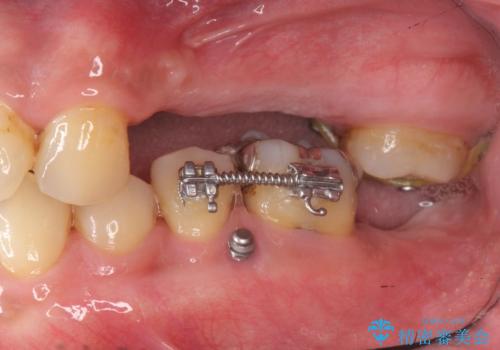

インプラント治療・セラミック治療を含む 全顎的虫歯治療

- 「 仕事が忙しく、虫歯を放置しすぎてしまった。この際全てきっちりと治したい。」と来院されました。

・歯の欠損

・虫歯

・深い虫歯

・欠損の放置による対合歯の挺出

・咬合平面の乱れ

・感染根管

以上のような問題を、徹底的な虫歯治療、歯周外科、インプラント治療、部分矯正治療、精密根管治療を用いてひとつずつ解決ししっかりと長期的に食事を楽しめるような口腔内環境の再構築を目指します。